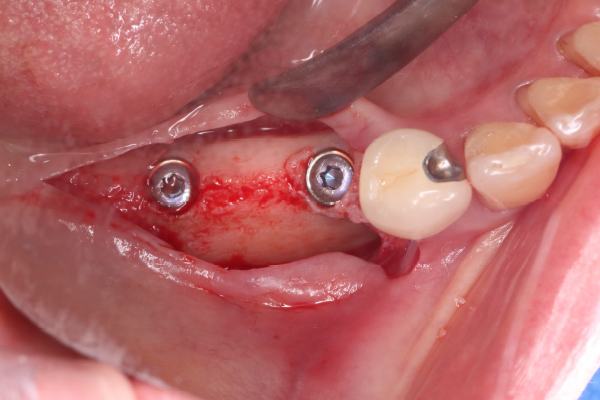

4. 骨再生手術後6ヶ月

骨再生治療後は新生骨ができるまで6ヶ月間の治癒期間を設けます。6ヶ月後に良好な新生骨が形成されていればインプラントを埋入することができます。

術後6ヶ月で歯肉の凹みは改善し、エックス線写真でも新生骨の形成が認められました。

5. インプラント埋入手術

インプラント埋入が可能な良好な骨形成が認められたため、インプラントを埋入しました。